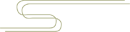

虽然我们说「 T1 序列看解剖,T2 序列看病变 」,但腰椎 MR 最重要的两个序列是 T2 序列矢状位 + T2 序列轴位(横断面)。矢状位序列帮助确定是哪个椎间盘,之后的评估将在轴位完成。

矢状面序列用以确定椎间盘位置

腰椎间盘轴位的解剖结构:腰椎间盘由三部分组成,中间是髓核,髓核之外包围着一圈纤维环,髓核上下各一软骨终板(也即正常椎间盘 = 上下软骨终板 + 纤维环 + 髓核)。

腰椎间盘 MR 评估需注意髓核、纤维环、后纵韧带等结构与神经根及硬膜囊的关系。